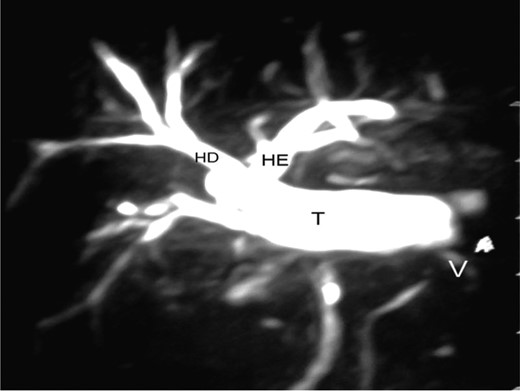

The patient was submitted to surgical intervention. Inspection showed a small fistula (probably the duct of Luschka [6]) in the gallbladder bed, the common hepatic duct was sectioned with loss of substance between segments, and the proximal and distal stumps were ligated with cotton suture. Next, catheterization of the fistula in the duct of the gallbladder bed was performed with a No. 4 Levine catheter. Cholangiography showed moderate dilatation of the intrahepatic bile duct and a sudden obstruction in the common hepatic duct 1 cm from the confluence of the hepatic ducts, corresponding to bile duct injury classified as Bismuth II (Fig. 1).

Right hepatic duct (RH), left hepatic duct (LH) and obstructed common hepatic duct (O).